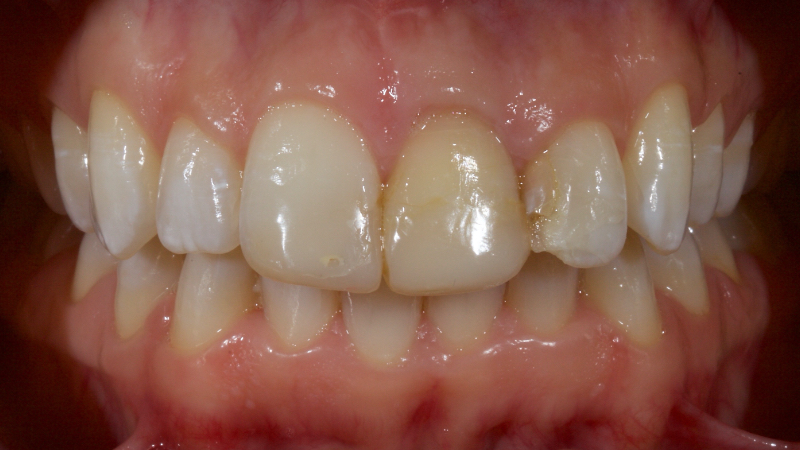

Historically, discolored anterior teeth were treated with indirect ceramic restorations, such as crowns or veneers. This can be illustrated in the case shown in Figure 1, where the discolored left central incisor (2.1), along with two other incisors, was treated with lithium disilicate ceramic veneers (Fig. 2). More recently, direct composite materials that incorporate specialized “opaquers” have also been utilized for treatment.